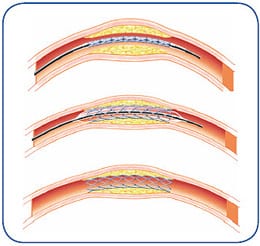

Angioplasty — a special catheter that has a balloon on one end is advanced into the diseased artery. This is temporarily inserted through the narrowed artery and inflated to flatten the plaque against the artery wall, opening the artery and restoring blood flow.

Stent placement —a stent is a small, expandable,  mesh-like tube that supports the artery and helps to keep it open. Implanting a stent does not require open surgery. The doctor inserts a catheter into an artery in your arm or leg, similar to the balloon angioplasty procedure. A specially designed catheter delivers the stent to the narrow area in the artery. The stent is expanded, flattening the plaque against the artery wall and holding the artery open with a mesh tube. The catheter used to deliver the stent is then removed, but the stent stays in your artery permanently to maintain healthy blood flow.

mesh-like tube that supports the artery and helps to keep it open. Implanting a stent does not require open surgery. The doctor inserts a catheter into an artery in your arm or leg, similar to the balloon angioplasty procedure. A specially designed catheter delivers the stent to the narrow area in the artery. The stent is expanded, flattening the plaque against the artery wall and holding the artery open with a mesh tube. The catheter used to deliver the stent is then removed, but the stent stays in your artery permanently to maintain healthy blood flow.

Atherectomy — a specialized catheter that modifies the plaque in the arteries. Unlike angioplasty and stenting, which are designed to move plaque to the sides, atherectomy involves cutting and removing or sanding down the plaque from the artery, restoring normal blood flow.